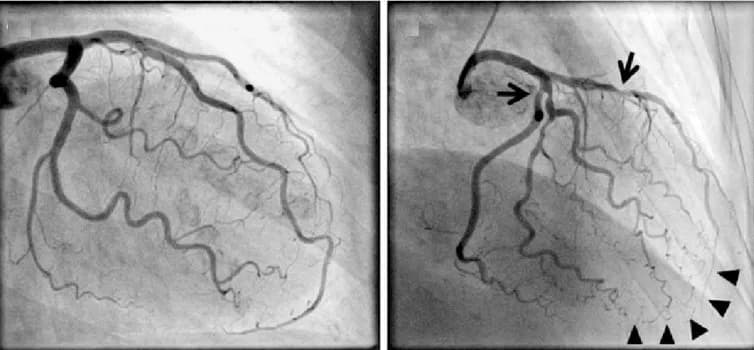

Chụp Động Mạch Vành: Giải Đáp Thắc Mắc và Can Thiệp Mạch Vành

Bệnh tim mạch, đặc biệt là bệnh động mạch vành, đã trở thành một trong những nguyên nhân hàng đầu gây tử vong tại Việt N...